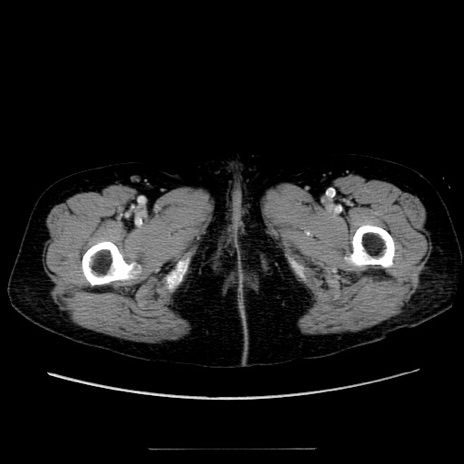

症例5(横断像)

【症例】70歳代女性

【主訴】お腹が張る

【現病歴】1週間くらい前から腹部膨満の自覚あり。昨日夜から増悪したため、本日救急外来受診。

【身体所見】意識清明、BT 36.5℃、BP 165/106mmHg、HR 80bpm、SpO2 98%、腹部:膨満、軟、自発痛・圧痛なし、触診にて不快感あり、腸蠕動音:減弱

【データ】WBC 12600、CRP 1.04